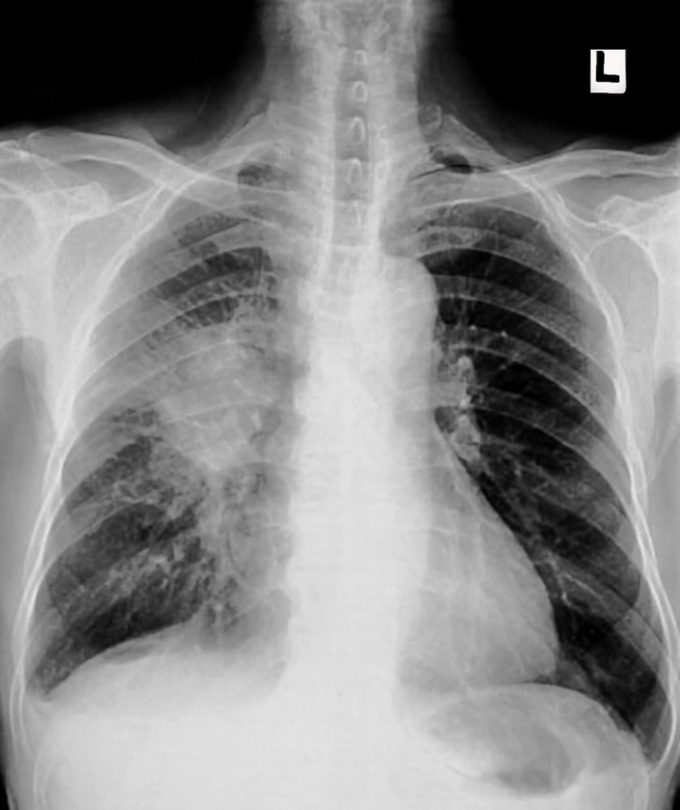

Lung cancer

This brutal disease is the leading cause of cancer death in men and women. In 2020, there will be about 228,820 new cases of lung cancer diagnosed in the United States, and 135,720 people will die from this disease, according to the American Cancer Society. The single biggest risk factor is no surprise, so don’t smoke—and if you do, quit by whatever means necessary.

Lung cancer screening remains extremely underutilized, says Nicholas Rohs, MD, a hematologist/oncologist at Mount Sinai Hospital in New York City. Low-dose CT scans can identify lung cancer when it’s in its most treatable forms. Screening doesn’t make sense for everyone, but for those at high risk it saves lives, he says. “If you are aged 55 to 80 and have smoked a pack or day for 30 years and you get screened, you are 20 percent less likely to die from lung cancer.” Talk to your doctor to see if this type of screening is right for you.

It’s a whole new day when it comes to treating and beating lung cancer, he says. “Genomics has revolutionized the face of lung cancer. We can now subtype lung cancers and choose treatments based on specific characteristics of the tumor,” he explains. “Targeted therapies are oral, well-tolerated startlingly effective.”